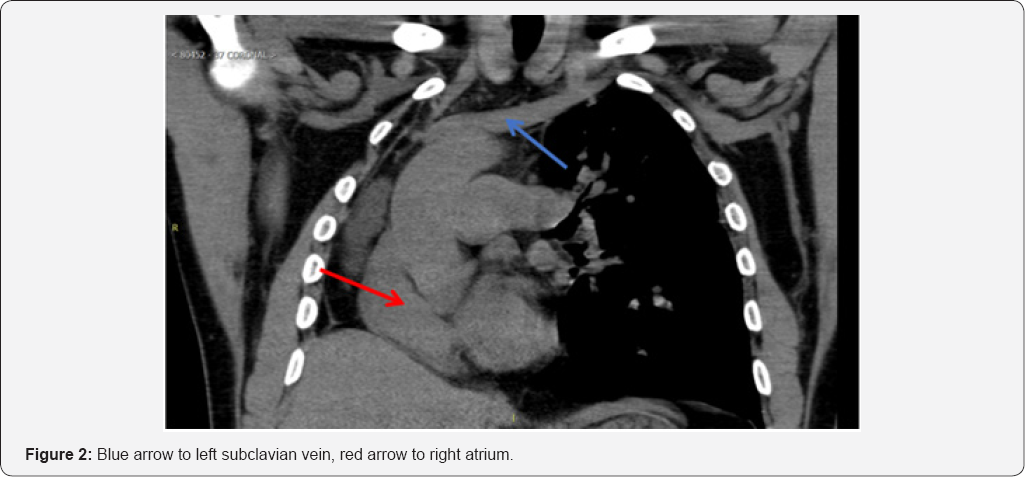

A CT scan of the thorax showed findings consistent with the post-pneumonectomy-like syndrome (Figure 1 & 2). Subsequent Pulmonary Function Tests: showed severe airway obstruction, without response to bronchodilators and severely decreased total lung capacity and diffusing capacity, EKG: sinus rhythm.

The postpneumonectomy-like syndrome occurs when an insult (infectious or otherwise) destroys lung parenchymal tissue (called autopneumonectomy), followed by a compensatory overexpansion of the contralateral lung, which results in mediastinal shifting [1,2].

In our patient with the postpneumonectomy-like syndrome, access through the cephalic vein and the superior vena cava to advance the RV lead was impossible due to mediastinal and heart shifting to the right. In cases with such distorted thoracic or vascular anatomy, several maneuvers to facilitate RV lead placement have been reported. Among them, manual reshaping of the stylet into a U-shaped stylet depends on thoracic anatomy (which necessitates considerable maneuvering) [4], ventricular lead placement in the left ventricular branch of the coronary sinus, and use of an atrial "J" stylet for ventricular lead placement.